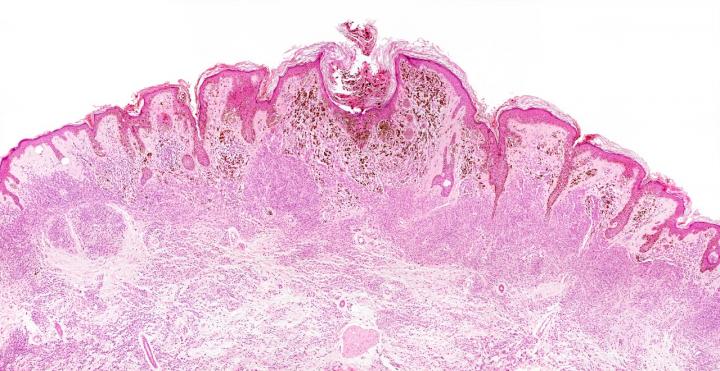

image: The study found that melanoma cells (above) pass through the lymph nodes and pick up a protective coating, allowing them to survive high levels of oxidative stress and go on to form distant tumors.

The study, published today in Nature, found melanoma cells that pass through the lymph nodes pick up a protective coating, allowing them to survive high levels of oxidative stress in the blood and go on to form distant tumors.